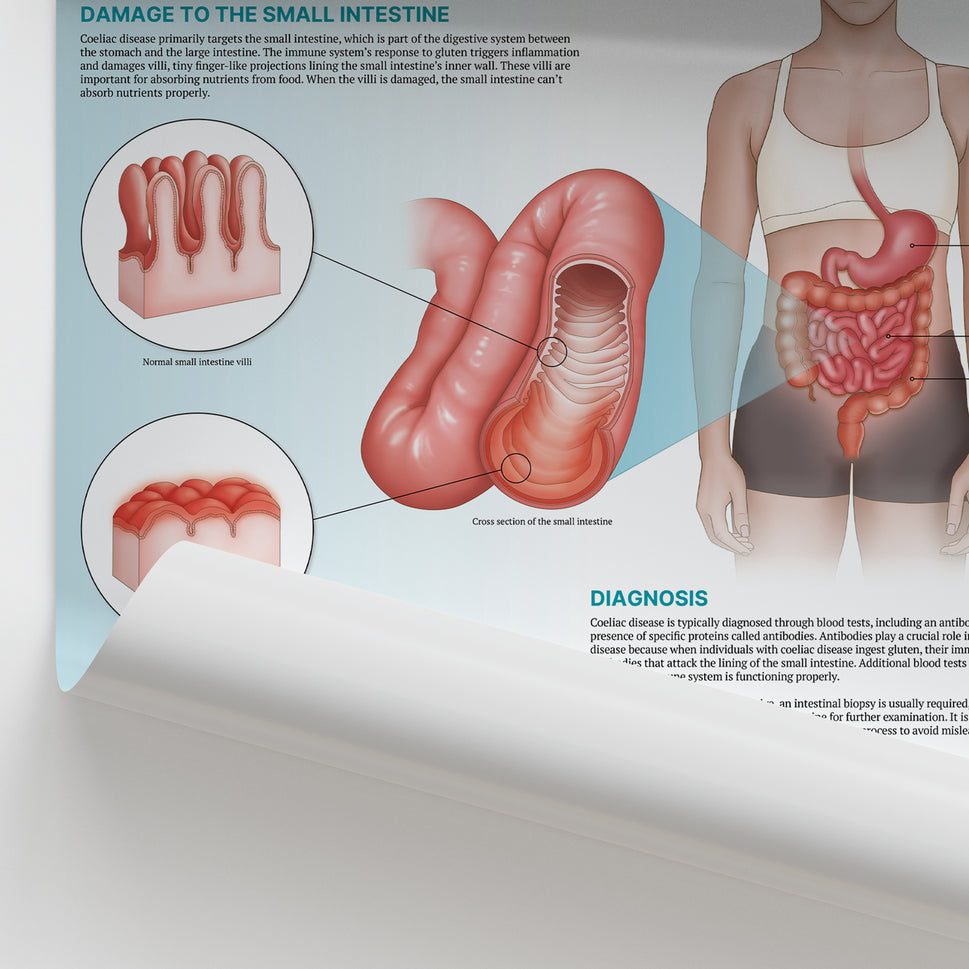

Enhance medical education with our collection of digestive system anatomical models including the stomach, liver, gallbladder, pancreas & colon models. Discover the anatomy of healthy organs as well as common gastrointestinal diseases such as stomach ulcers, gallstones and liver cirrhosis. Our digestive system anatomy posters are ideal for study and patient education.

At AnatomyStuff we stock a diverse range of digestive system anatomical models to suit your training needs. From budget models and affordable medical education posters to highly advanced 3D printed bowel models, you can transform medical training and patient education. As well as our own exclusive collection, we are proud resellers of 3B Scientific, Anatomy Lab, Denoyer-Geppert Science Company, ESP Models, Erler Zimmer and GPI Anatomicals. Explore our exclusive collection of digestive system anatomy charts, posters, fine art prints and digital anatomy study guides. Discover the anatomy of key organs like the liver, stomach, pancreas and bowel as well as the pathophysiology of common conditions like peptic ulcer disease, coeliac disease, IBD and much more. We have anatomy posters suitable for school children all the way up to medical degree level. From a liver anatomy poster to a digital study guide all about common GI disorders, find exactly what you need right here to enhance medical training and patient education.